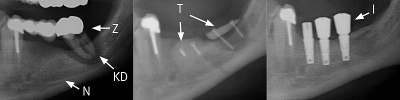

Röntgenverlauf Sinuslift:

Die Röntgenbilder zeigen einen Kieferaufbau eines durch Zahnentzündung (Z) entstandenen Knochendefekts (KD) in Nervnähe (N). Die Transplantate (T) aus dem Kieferwinkel wurden mit kleinen Schrauben fixiert. Nach Heilung erfolgt die weitere Implantatversorgung (I).